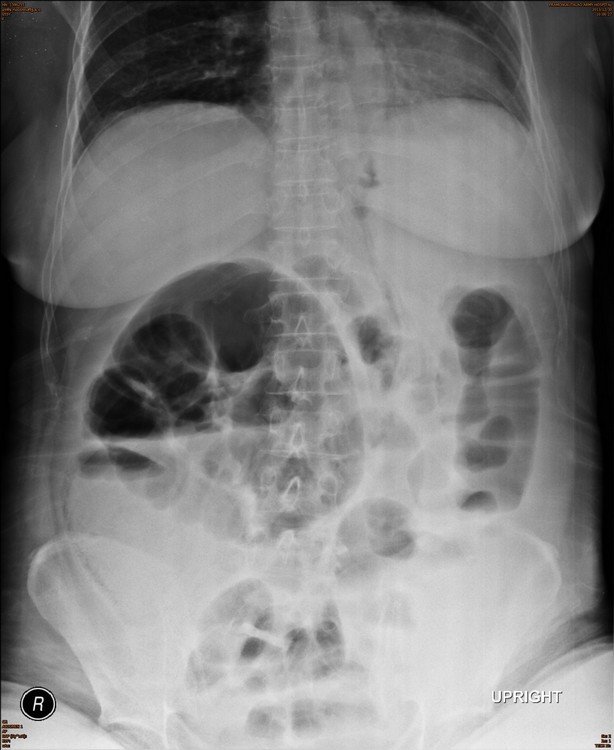

What is the positive finding in the plain abdominal radiograph?

Answer : A. Large bowel dilatation

Answer : C. Air in the bowel wall or pneumatosis intestinalis

This case show curvilinear gas in the cecal wall